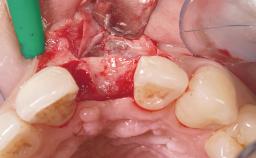

A 39-year-old male patient presented with a chief complaint of discomfort and gingival discoloration around his maxillary left central incisor. He was in good general health and was a non-smoker. His past dental history was significant because of the traumatic fracture of tooth 21 in a sporting accident at age 13. Initial dental treatment included endodontic therapy and a full-coverage restoration. The patient became symptomatic 5 years later, when structural failure of the tooth resulted in the dislodgment of the crown. Endodontic retreatment, apical surgery, and post-and-core restoration were performed.

Placement Protocol Early or late implant placement

Bone Volume Deficient horizontally, requiring prior grafting